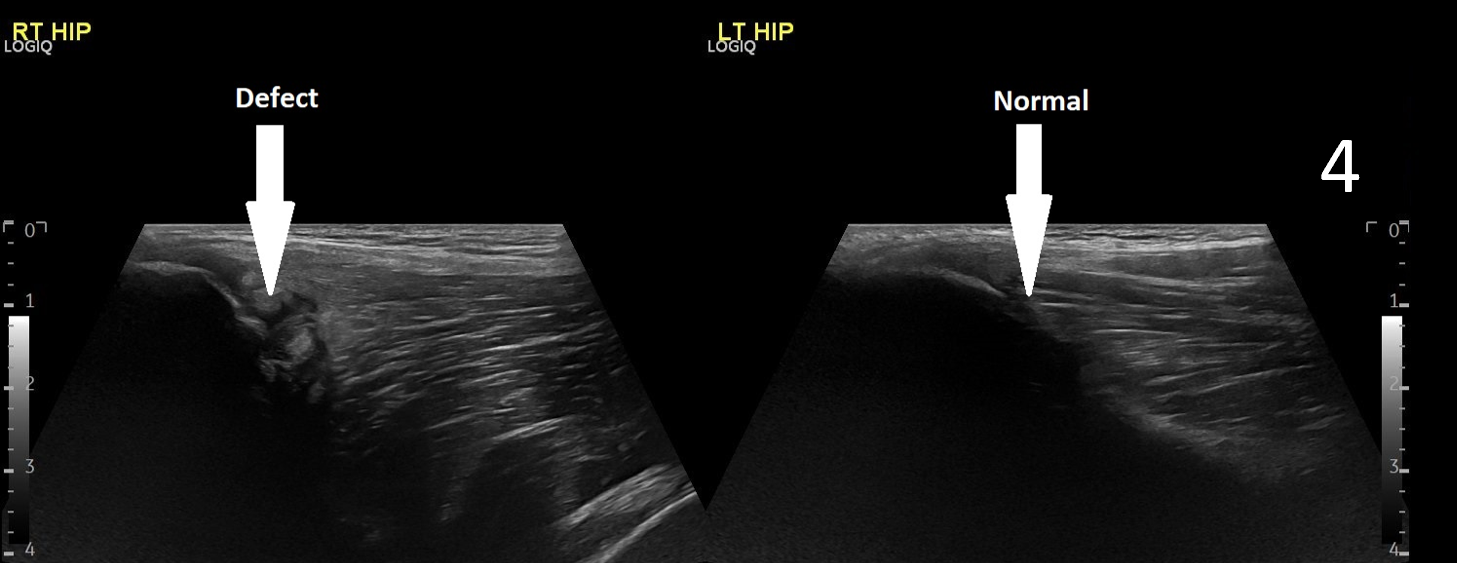

A 17-year-old male presented with severe pain in his right groin. He felt a ‘pop’ in his right groin whilst sprinting and was struggling to weight-bear. A radiograph excluded any bony abnormality (Figure 1) and an ultrasound scan showed no evidence of inguinal or femoral hernia.

The patient was focally tender in the right iliac fossa at the level of the anterior superior iliac spine (ASIS). At this site, there was muscle fibre disruption and a haematoma at the insertion of the sartorius tendon with minimal retraction (Figure 2). There was cortical irregularity at the ASIS and a bony fragment within the retracted tendon and also neovascularisation here on power Doppler (Figure 3). On comparison to the contralateral side, there was altered architecture of the sartorius muscle with a clear defect while the left side looked normal (Image 4). Ultrasound appearances in keeping with a sartorius tendon avulsion. This was treated conservatively with rest, analgesia and a return to normal activities after two months. Surgical interventions are uncommon and are reserved for when the fracture fragment has migrated more than 3cm.

This injury is associated with young athletes plus young rugby and football players.